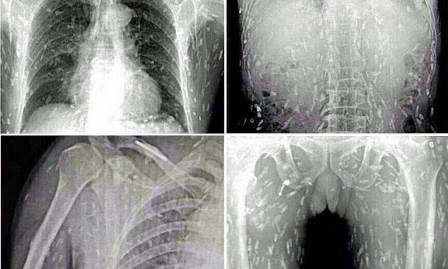

Le cronache recenti hanno acceso i riflettori sul verme Anisakis, il parassita del pesce fresco, incubo di tutti gli amanti del sushi. Tantissimi i casi di annidamento nel corpo umano registrati in Italia, l'ultimo, in ordine cronologico, qualche giorno fa a Bergamo, dove uomo una volta terminata la cena a base di pesce avrebbe cominciato ad avvertire prurito in tutto il corpo, da lì la corsa in ospedale con l'orribile scoperta di avere lo stomaco infestato dai vermi. Nel pesce ingerito, dunque, non preventivamente congelato a basse temperature erano presenti migliaia di uova di Anisakis.